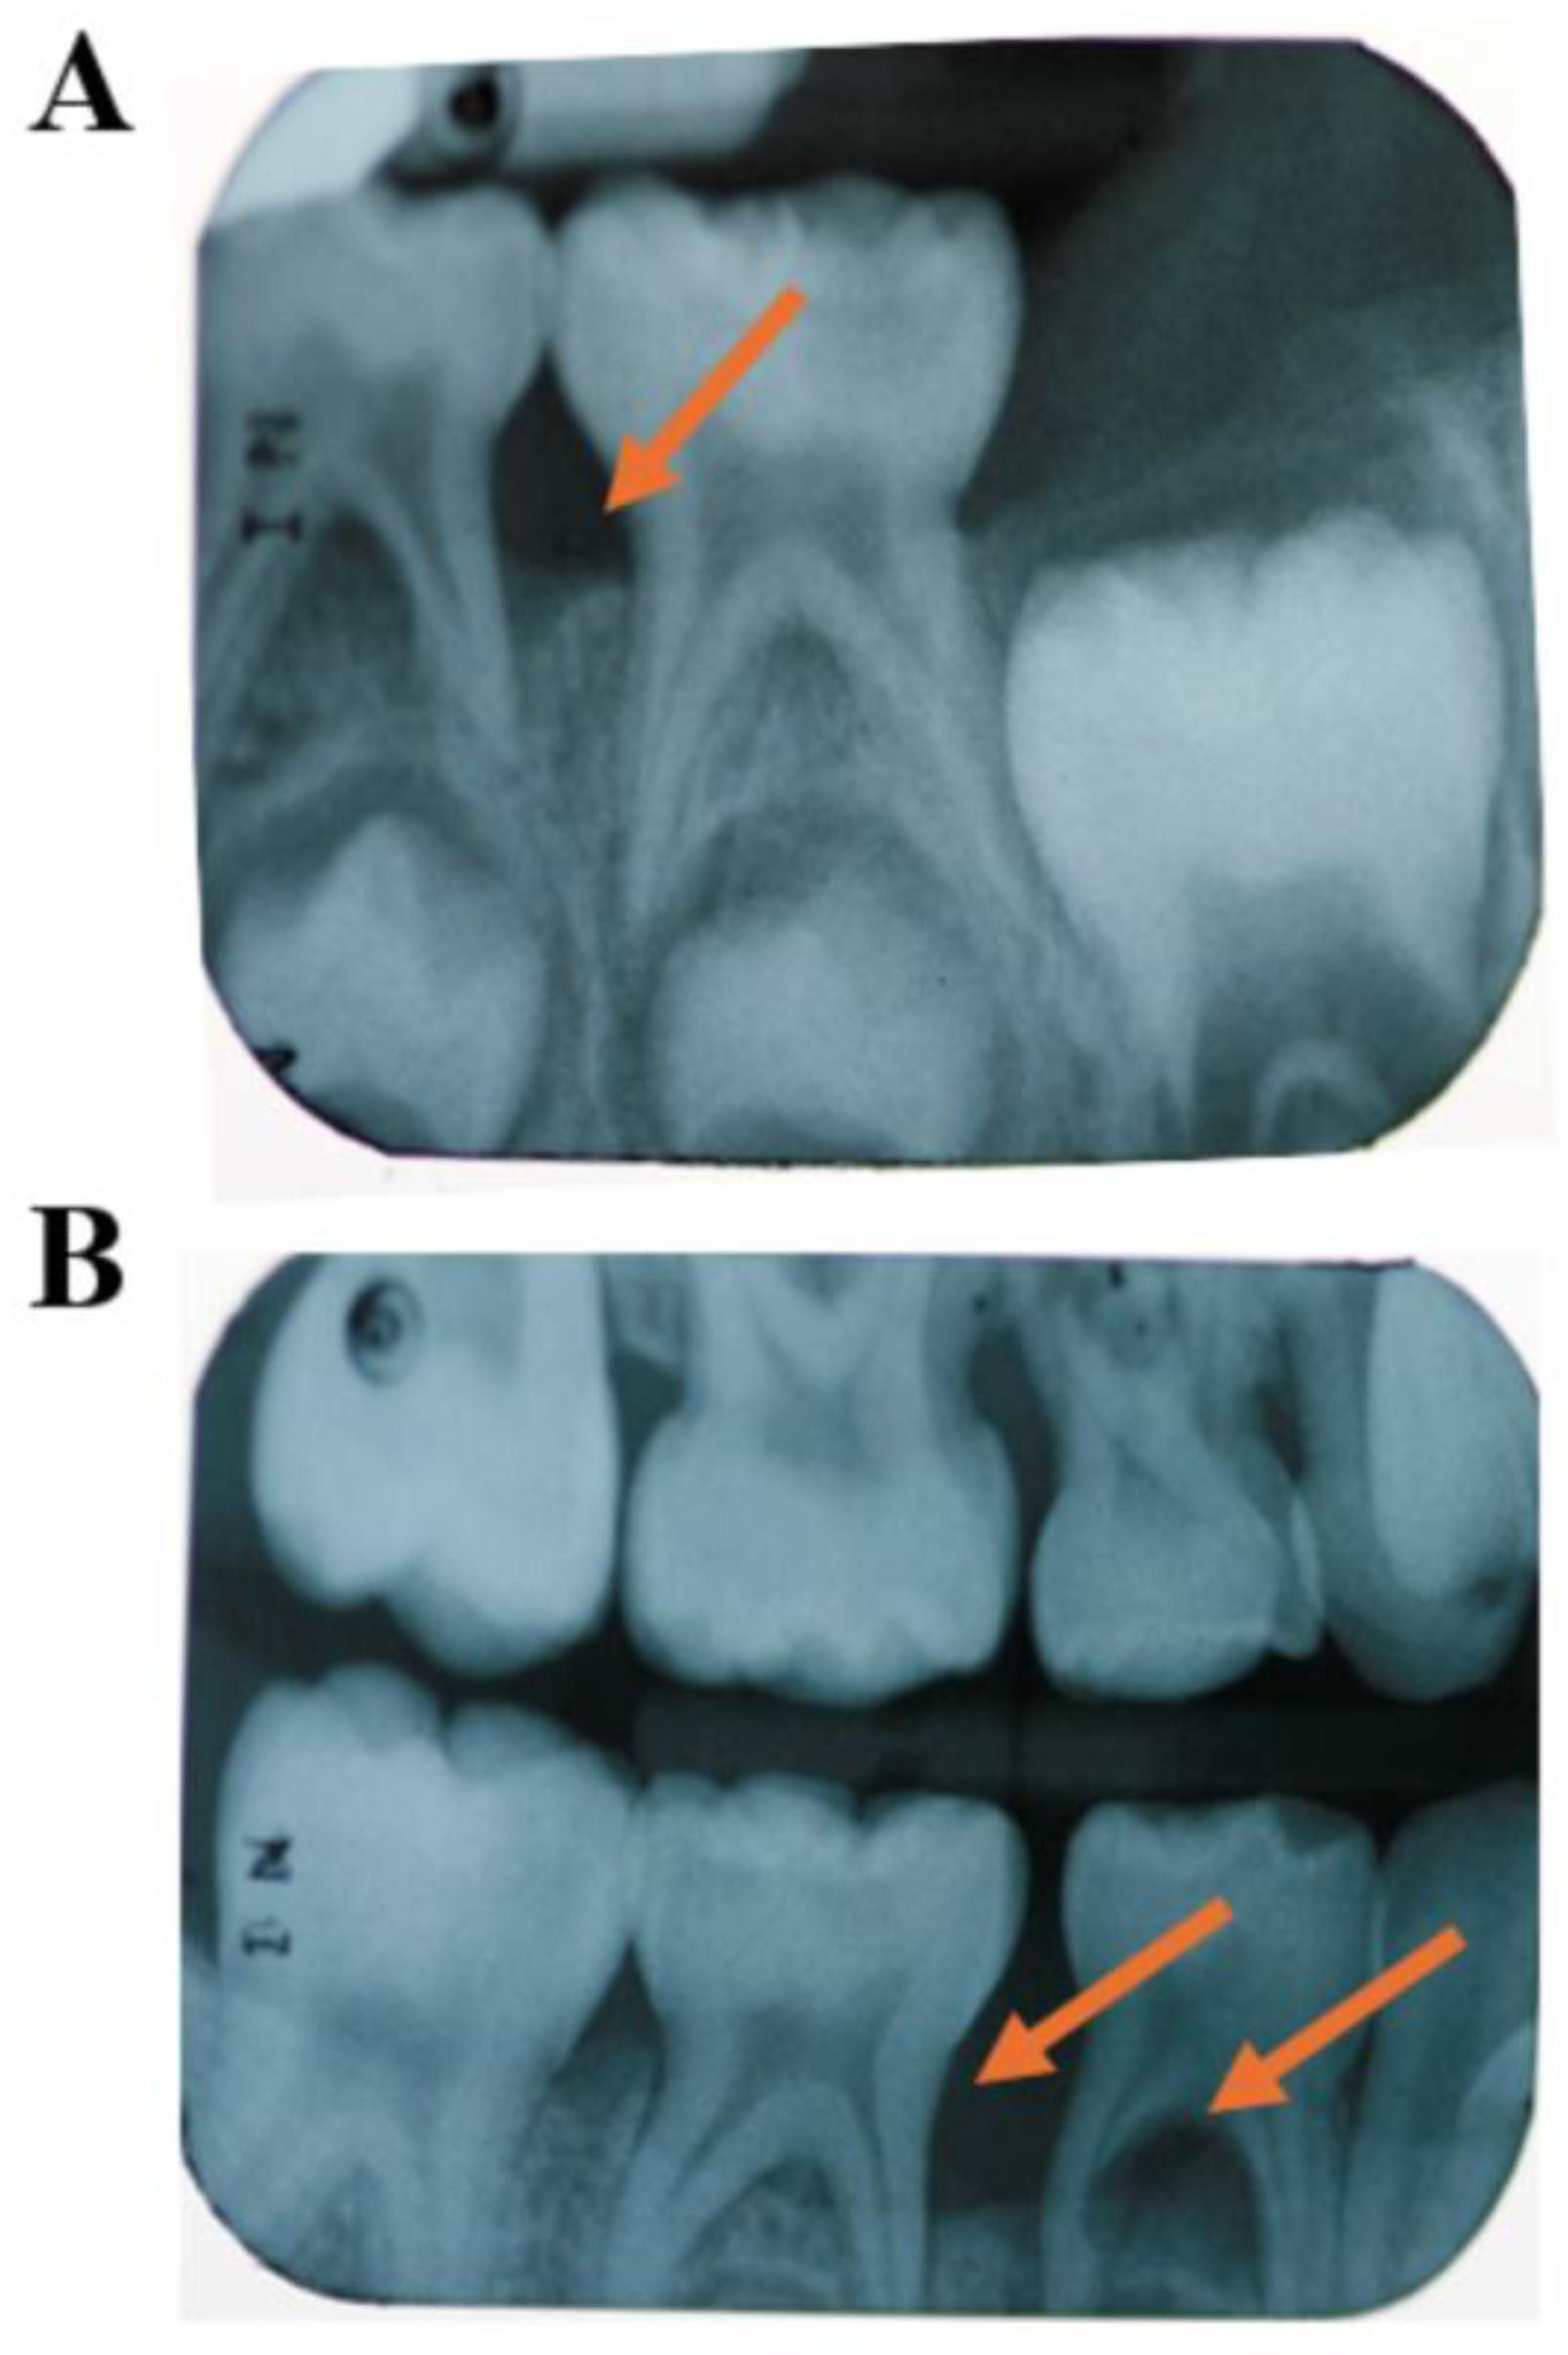

Figure 6.

Retrospective evaluation of radiographs of a sibling of a C-MIP patient. Childhood radiographic records show initial bone loss at the first primary molars at five years old (A). The disease progressed fast and spread to the second primary molars at age 6 (orange arrows) (B). (Source of the image [16]).